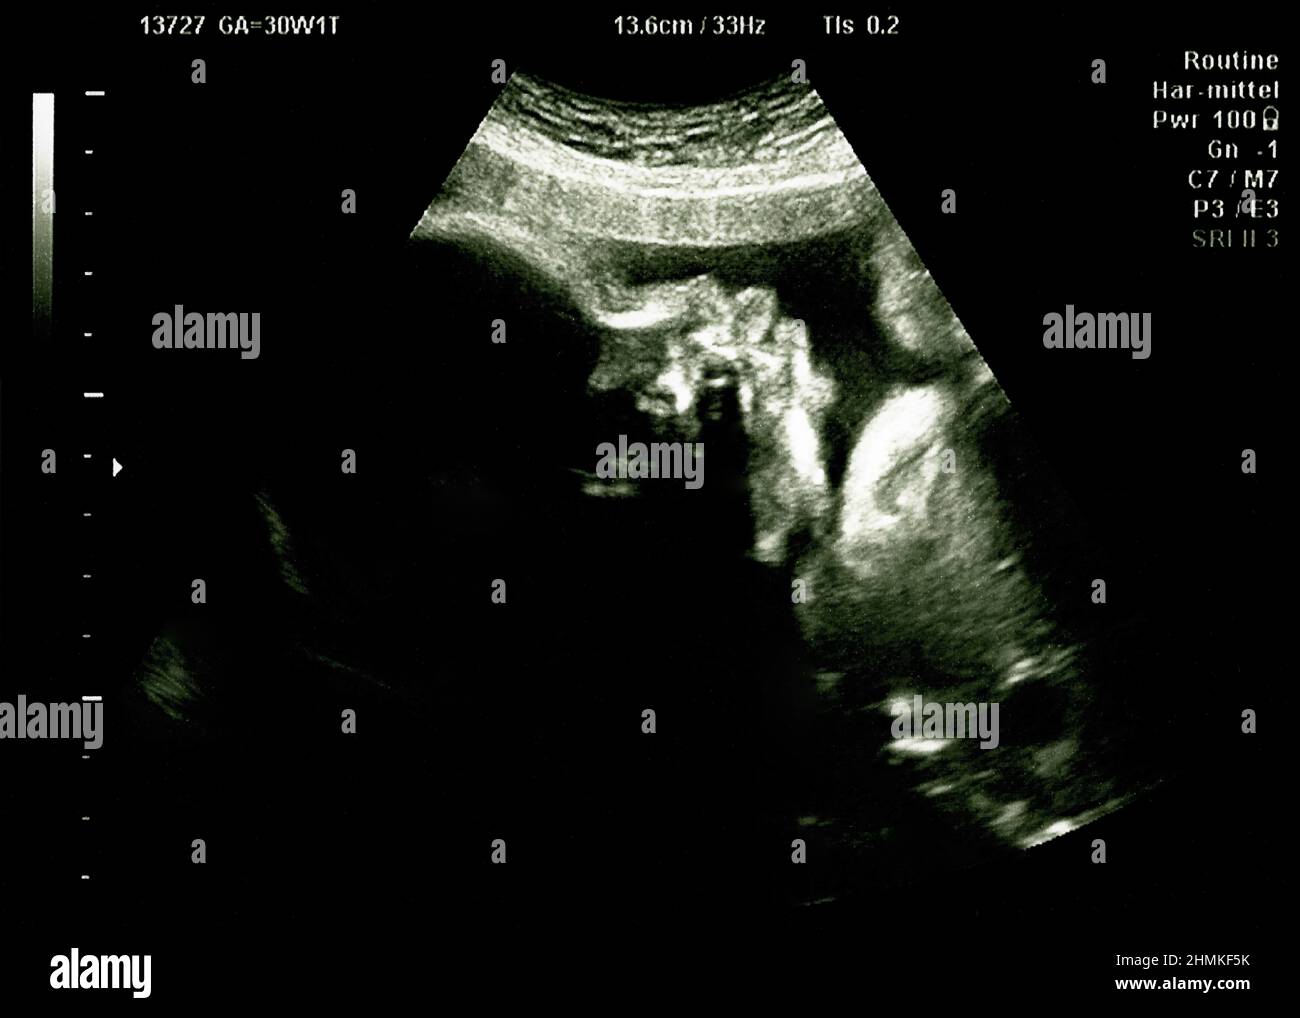

Baby Head Down Position Ultrasound . the ideal fetal position for labor is when the fetus is head down, facing your back, with its chin tucked to its chest and. how to tell baby’s position in the womb: traditionally, fetal head position can be determined during labor after the cervix dilates by digital examination by palpation. Remember that the best position for a vaginal birth is head down (called vertex). In the final weeks of pregnancy, your healthcare provider will feel your lower abdomen with their hands to assess the positioning of the baby. This position means that your baby is head down but facing the opposite direction. your healthcare provider can determine if your baby is in cephalic presentation by performing a physical exam and ultrasound. when a baby is head down, face down, the medical term for it is the cephalic occiput anterior position.

Baby head on ultrasound scan in hospital check, Echography Scan Stock Photo Alamy Baby Head Down Position Ultrasound your healthcare provider can determine if your baby is in cephalic presentation by performing a physical exam and ultrasound. This position means that your baby is head down but facing the opposite direction. In the final weeks of pregnancy, your healthcare provider will feel your lower abdomen with their hands to assess the positioning of the baby. the. Baby Head Down Position Ultrasound.